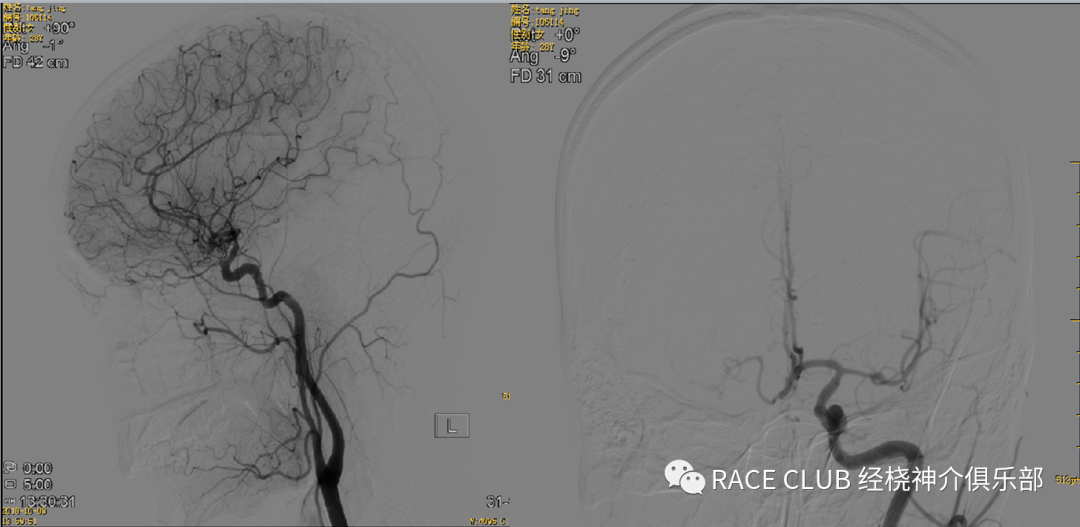

•侧位:(42)上端去头皮,下端露出分叉处,最好看到导管头端,图像在正中间

•正位:(27或31)矢状缝对齐,汤氏位,错开眉弓对大脑中动脉影响

造影导丝是什么全脑血管造影术_https://www.jmylbn.com_新闻资讯_第12张

•正位:(48)矢状缝对齐,稍汤氏位,上端平人字缝,下端露出椎动脉开口,看到导管头

•侧位:(31)左侧平枕骨隆突,下平2/3椎体